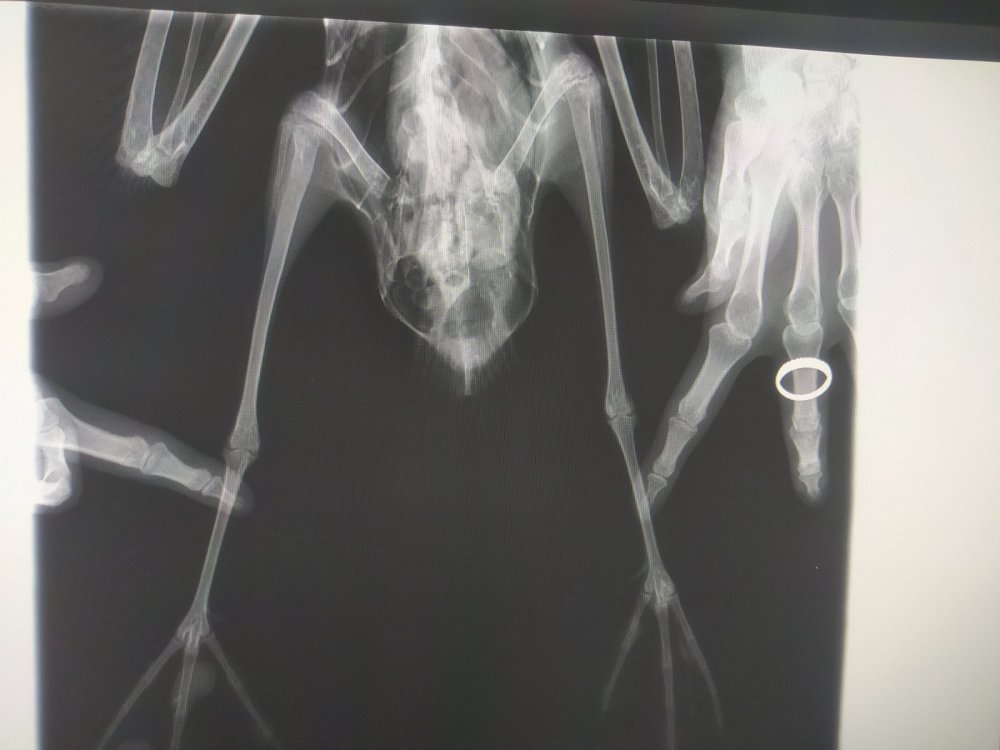

Четрые дня назад на участке нашла птицу, убегает, клюется, самостоятельно ест и пьет. В первый день была покормлена 2 варёными яйцами, все остальные дни только размороженная рыба. Днём гуляет по участку, на ночь убираю в картонную коробку. Думаю это серебристая или средиземноморская чайка. Вес около двух кг. На рентгене переломов не замечено

Короче, с костями птицы все было нормально, оба крыла рабочие, но.. Вот эта вот крохотная металлическая проволока проигнорированная мной на рентгене как артефакт её и убила(

Распорот кишечник, гнойный перетонит, тромб в сердце (скорее всего посмертный)